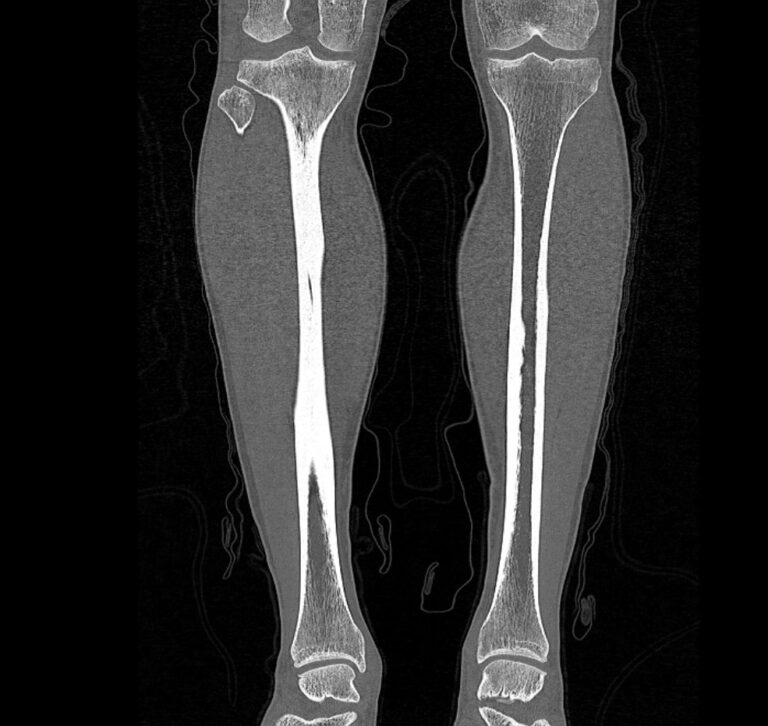

Наиболее информативным методом исследования костных структур и мягких тканей голени является мультиспиральная компьютерная томография. КТ относится к лучевым методам исследования и основана на применении ионизирующего излучения и последующей цифровой обработке данных, полученных при КТ-сканировании.

В наших медицинских центрах обследование области голени проводится на современных мультиспиральных компьютерных томографах последнего поколения TOSHIBA AQUILION. При помощи рентгеновских лучей аппараты послойно сканируют исследуемую область с толщиной среза от 0,5 мм. В результате получаются детальные снимки и цифровые трехмерные изображения в мельчайших подробностях. При этом пациент получает уменьшенную дозу рентгеновского облучения.

Мультиспиральная компьютерная томография позволяет оценить структуру костей голени, выявить переломы, воспалительные изменения, участки деструкции костной ткани, диагностировать опухолевые образования.